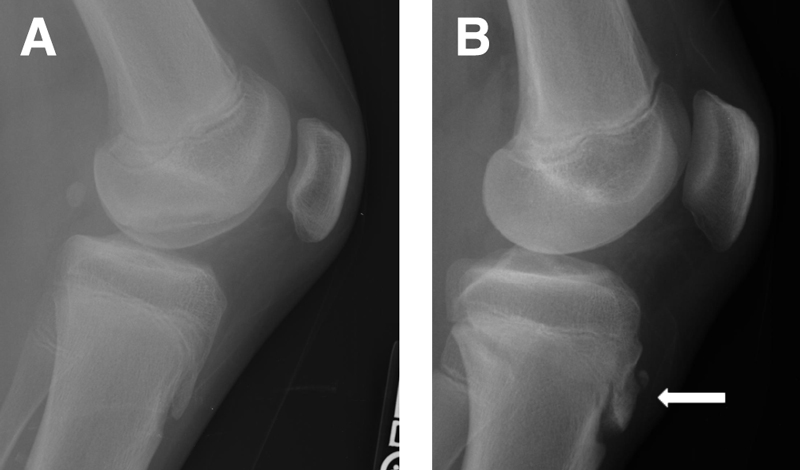

A história clínica e o exame físico, baseado na palpação local da proeminência óssea seguido por um raio-x é capaz de fechar o diagnóstico da doença. Alguns casos com recidivas ou sintomas mais graves a ressonância magnética pode ser solicitada para avaliar se durante o período de calcificação de uma das microfraturas não houve deslocamento de um fragmento.

(Imagem A) Demonstrando um raio-x normal. (Imagem B) Demonstrando a doença de osgood schlatter. (Imagem C) Ressonância magnética demonstrando a doença.